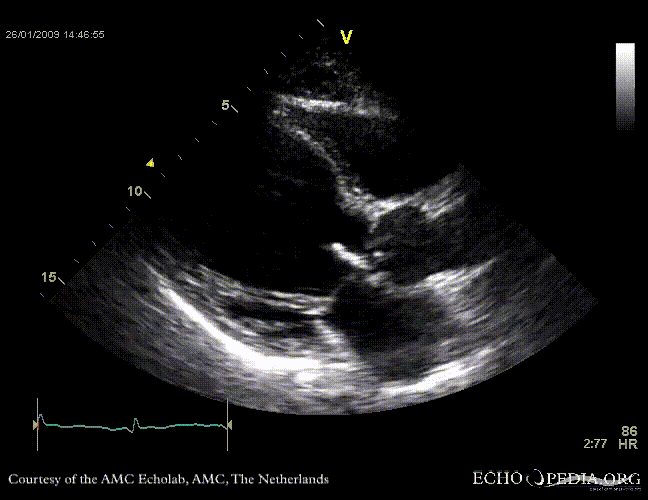

Aortic valve endocarditis with vegetation

Case description: This patient had endocarditis with an aortic valve vegetation

E00114.gif E00115.gif

PLAX showing an aortic valve vegetation PLAX Excentric aortic valve regurgitation